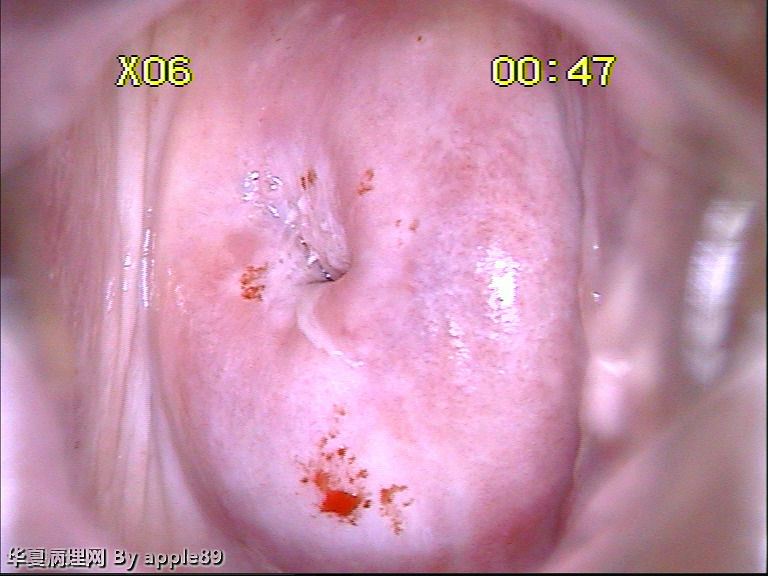

患者女,35岁,因急性粒细胞白血病做化疗,化疗后月经周期紊乱,自今年5月份来月经后就一直月经未来潮,既往月经规律,量正常,无痛经、腹痛等症状。患者育有三胎,已结扎。请妇科会诊,取了宫颈液基。3215

病人做阴道镜,没有看到明显醋酸白区域,随机活检了几块,由于组织受压变形,有点难看,不过补切之后,还是没发现啥问题。前两张是我从阴道镜报告上截的图,后几张是活检图

这个我也报的HSIL,但是活检结果挺郁闷……